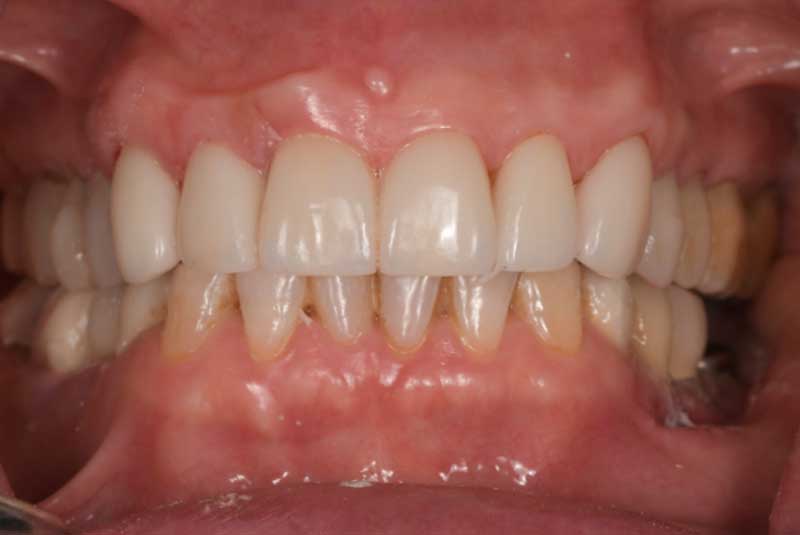

The patient had her implants placed 20 years ago. Four implants, particularly in the maxilla, were not positioned ideally for me to utilize and restore, while the four implants in the mandible were outdated and no longer functional. The patient's primary concern is to restore both function and aesthetics.

All on 6: Facial cut back (PFZ) Zirconia Full arch prosthesis for Maxilla and Mandible Before & After

All on 6 for both arches Implants (#3,4,6,11,13,14,18,21,22,27,28,31)